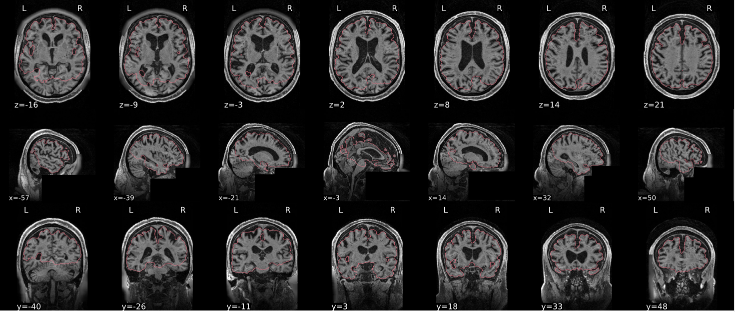

EPI ICA-based artefact removal

The fMRI data for each subject are decomposed into spatially independent components. Each component is represented by a spatial map and a time course. Some components represent noise, some signal. ICA AROMA is trained to automatically classify these components. Signal components are usually represented by low numbers of large clusters (some of which may represent known networks such as the Default Mode Network), located in the GM and away from WM, CSF, blood vessels, or the edges of the brain. Signal components usually do not have a particular shape, while noise components may show banding or ring patterns. Signal components usually have low frequency (0.01-0.1 Hz) (i.e., few spikes on the left hand side of the power spectra plot), while noise high frequency, or very low. The time series of signal components is oscillatory and fairly regular, while in noise we may see sudden spikes or differing patterns (see Griffanti et al., 2017. Hand classification of fMRI ICA noise components. NeuroImage).

Some examples are presented below. For each component, there is a spatial map (on the left), the time series (top plot on the right) and the power spectra (bottom plot on the right). Of note, ICA AROMA errors cannot be ‘fixed’, as it automatically classifies the components.

We don’t expect you to check all the components for every subject. Rather, try to eyeball the report and see whether generally clusters that should be signal (according to the description above) are coloured in green. If you think that ICA AROMA performed poorly, check the other quality metrics for that subject to decide whether they should be excluded.

Example of a good subject

- Components correctly classified in noise (red) and signal (green), conservative classification (uncertain components classified as signal).

Example of a bad subject

- ICA AROMA might have performed poorly if it classified all/most of the components as noise, when some of them could have been signal. These types of errors are more likely to occur in task fMRI with block designs, whereby some task-related activity may be classified as motion. In resting state, try to look for common large brain networks such as the default mode network/salience network. If they have been classified as noise, ICA-AROMA might have not performed well. It is possible that ICA AROMA classified all/most of the components as noise if the subject was particularly problematic (lot of motion, artefacts)

- Components that look like rings, bandings or stripes are usually acquisition-related artefacts (e.g., interleaved acquisition, multi-band). The presence of these artefacts is not an issue by itself, but ideally these components should be classified as noise. Note that ICA AROMA was not trained on multiband data, so it is possible that it classifies some of these components as signal (nothing we can do about).

- We don’t expect you to check all the components for every subject. Rather, try to eyeball the report to get a general idea. If unsure, and there is a recurring issue across youdr dataset, please send us some screenshots.

- In case of uncertain components, it is preferable that ICA AROMA behaved conservatively, and did not remove these components, because they may contain some signal

NOTE: If you think that ICA AROMA performed poorly or the subject looks problematic, check the other quality metrics for that subject to decide whether they should be excluded.

Summary

| good | bad |

|---|---|

| Time series (at the top): no sudden jumps power (bottom) | More noise (red) than signal (green): - Occurs more often with block design - or “problematic” subject (lots of movement, lots of artefacts) rings, bands, artefacts - should be classified as noise |

| Spatial patterns are visible | |

| No sudden jumps/spikes | |

| No big spikes |